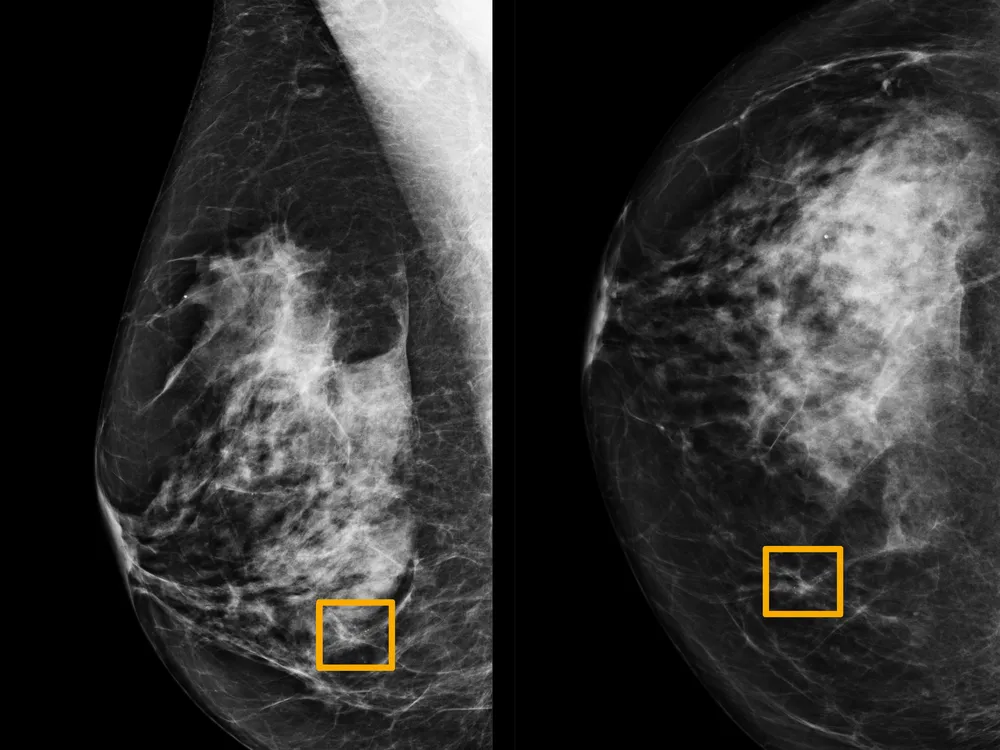

Suppose you want to be able to tell whether a patient has breast cancer or not.

Image source: Smithsonian Magazine